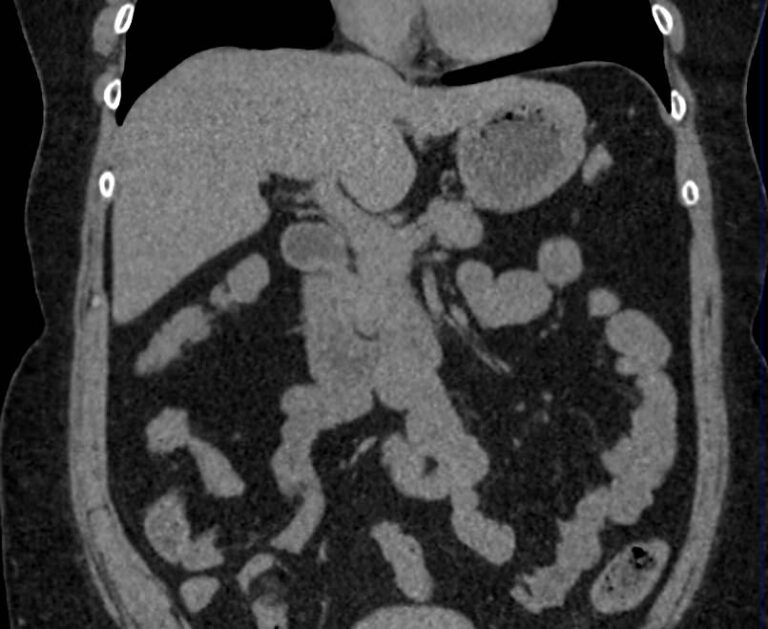

Мультиспиральная компьютерная томография (МСКТ) брюшной полости относится к современным лучевым методам исследования, с помощью которого можно оценить состояние органов брюшной полости (печени, желчного пузыря, поджелудочной железы, селезенки), прилегающих к ним кровеносных сосудов и лимфатических узлов.

С помощью мультиспиральной компьютерной томографии проводятся послойные рентгеновские снимки исследуемой области с толщиной среза от 0,5 мм. В нашей клинике исследование выполняется на компьютерном томографе экспертного класса TOSHIBA AQUILION CXL, который оснащен 128 детекторами, позволяющими получать за несколько секунд снимки брюшной полости с высокой точностью. Большое количество детекторов позволяет получить точные данные, при этом сократить время исследования и сделать минимальной лучевую нагрузку на пациента. Кроме того, инновационные технологии аппарата дают возможность сформировать объемную модель органа и окружающих структур, что также способствует проведению точной и достоверной диагностики.

При подозрении на опухоли, воспалительные процессы, гнойные очаги назначается КТ брюшной полости с внутривенным болюсным контрастированием. Для этого пациенту внутривенно вводится рентгеноконтрастное вещество на основе йода. Благодаря усиленному кровоснабжению препарат накапливается в структуре патологических образований и помогает врачу-рентгенологу выявить изменения в структуре внутренних органов.

Метод контрастирования помогает максимально точно выявить очаг патологии уже на начальной стадии, а также установить его локализацию, точные размеры, форму и особенности кровоснабжения.